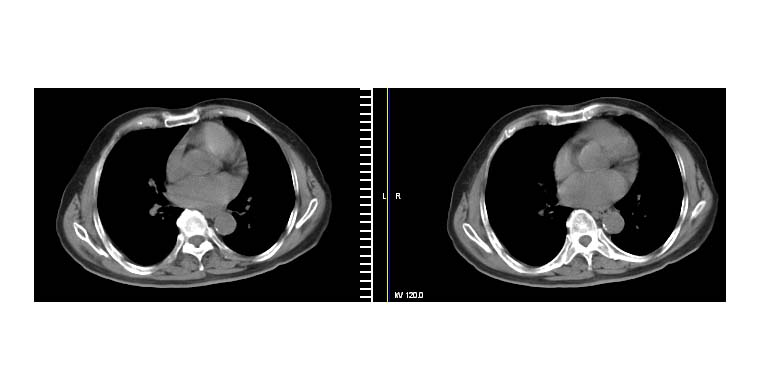

标题: CT11087:男性,82.咳嗽一周.抗炎治疗4-5天效果不明 [打印本页]

标题: CT11087:男性,82.咳嗽一周.抗炎治疗4-5天效果不明

病人年龄偏大,不除外为恶性病变。

考虑左上肺癌(病灶有分叶,毛刺)可能性大.

考虑左上肺周围性肺癌(实性病灶有分叶,毛刺)可能性大。